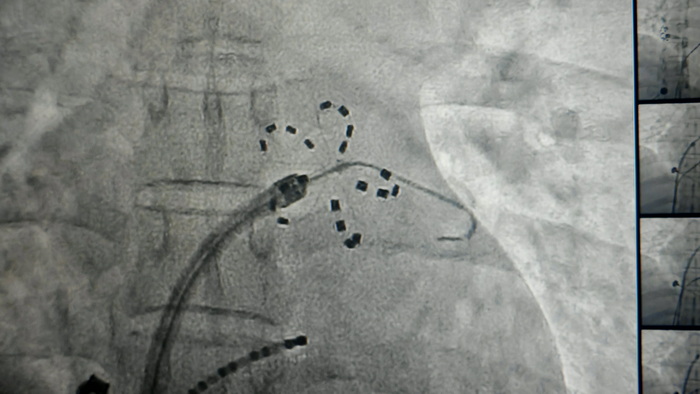

手术当天,在我院心血管内科电生理团队、麻醉科(手术室)技术骨干的紧密配合下,为一位深受房颤困扰的30余岁的年轻男性患者实施了PFA手术。术中使用心脏脉冲电场消融导管对肺静脉前庭进行了精准、高效的电隔离,患者术中生命体征平稳,术后恢复良好。

手术时影像资料